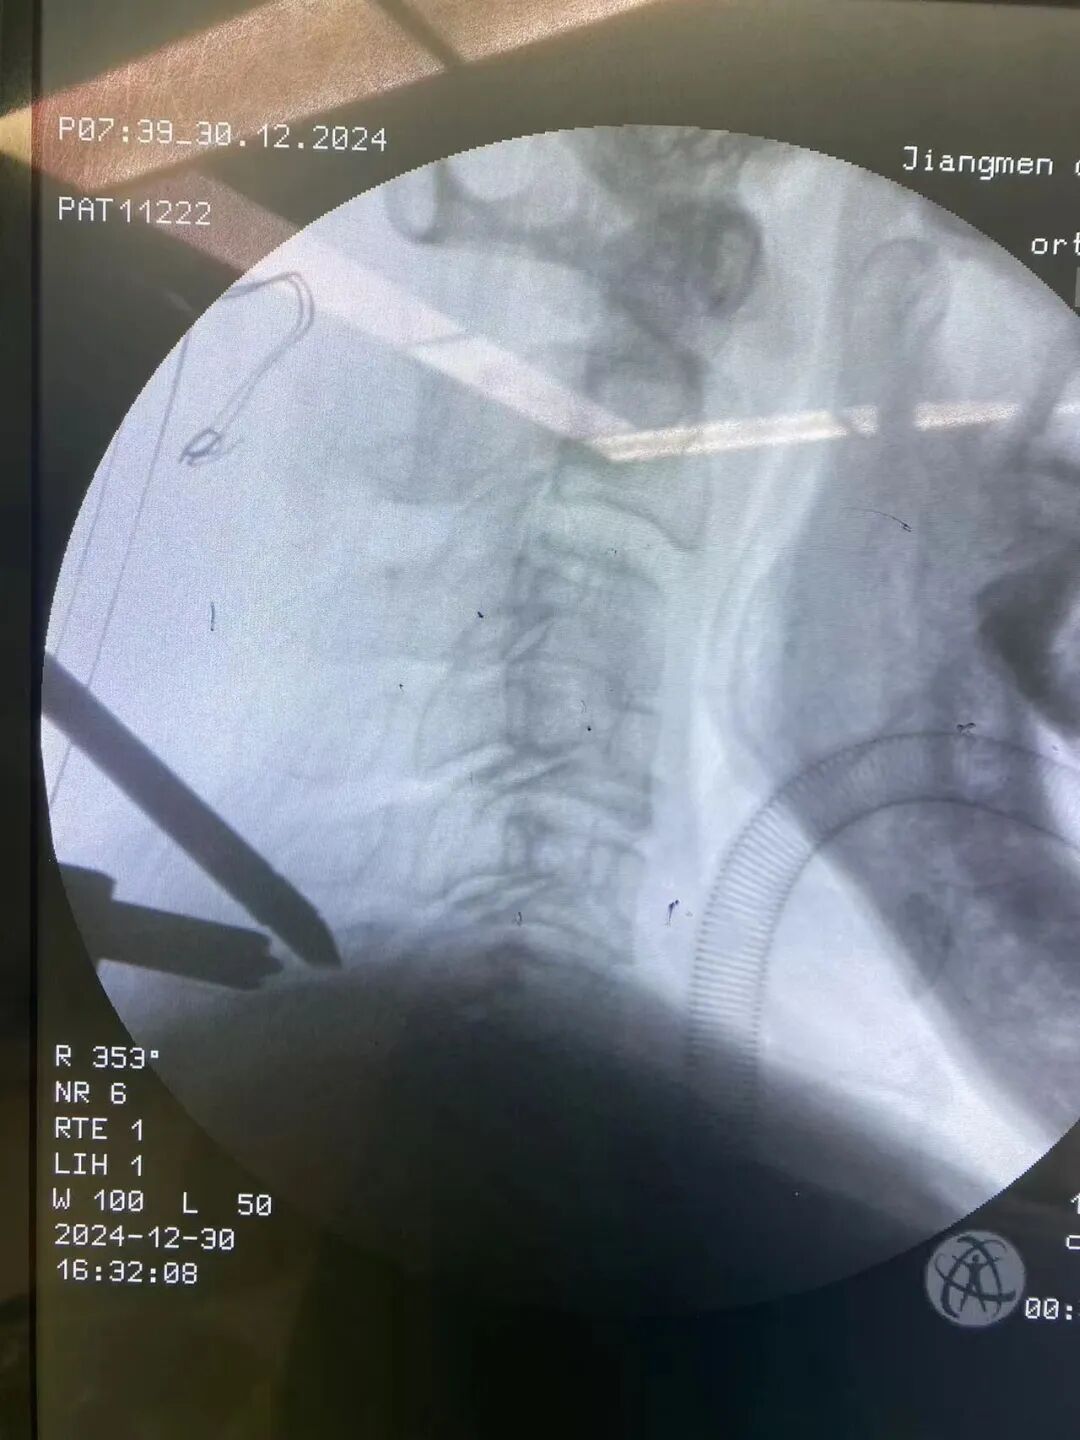

●江门首例颈椎UBE破难题

76岁的曾叔因为左上肢疼痛半年余前来江门市中心医院就诊,颈椎多节段病变,脊柱骨科团队应用最前沿的新技术结合神经根阻滞确定手术节段,UBE内镜微创治疗颈椎病,避免了开大刀及手术范围扩大,该术式在颈椎上的应用为江门首例,手术创伤小,患者恢复快,术后第一天就下地行走。